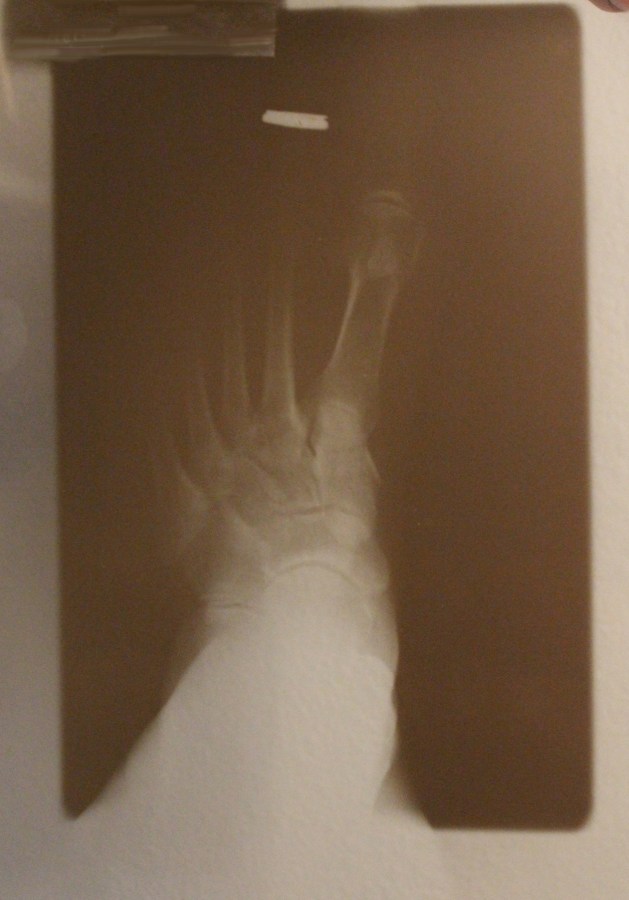

No broken bones, just a bruised ego.